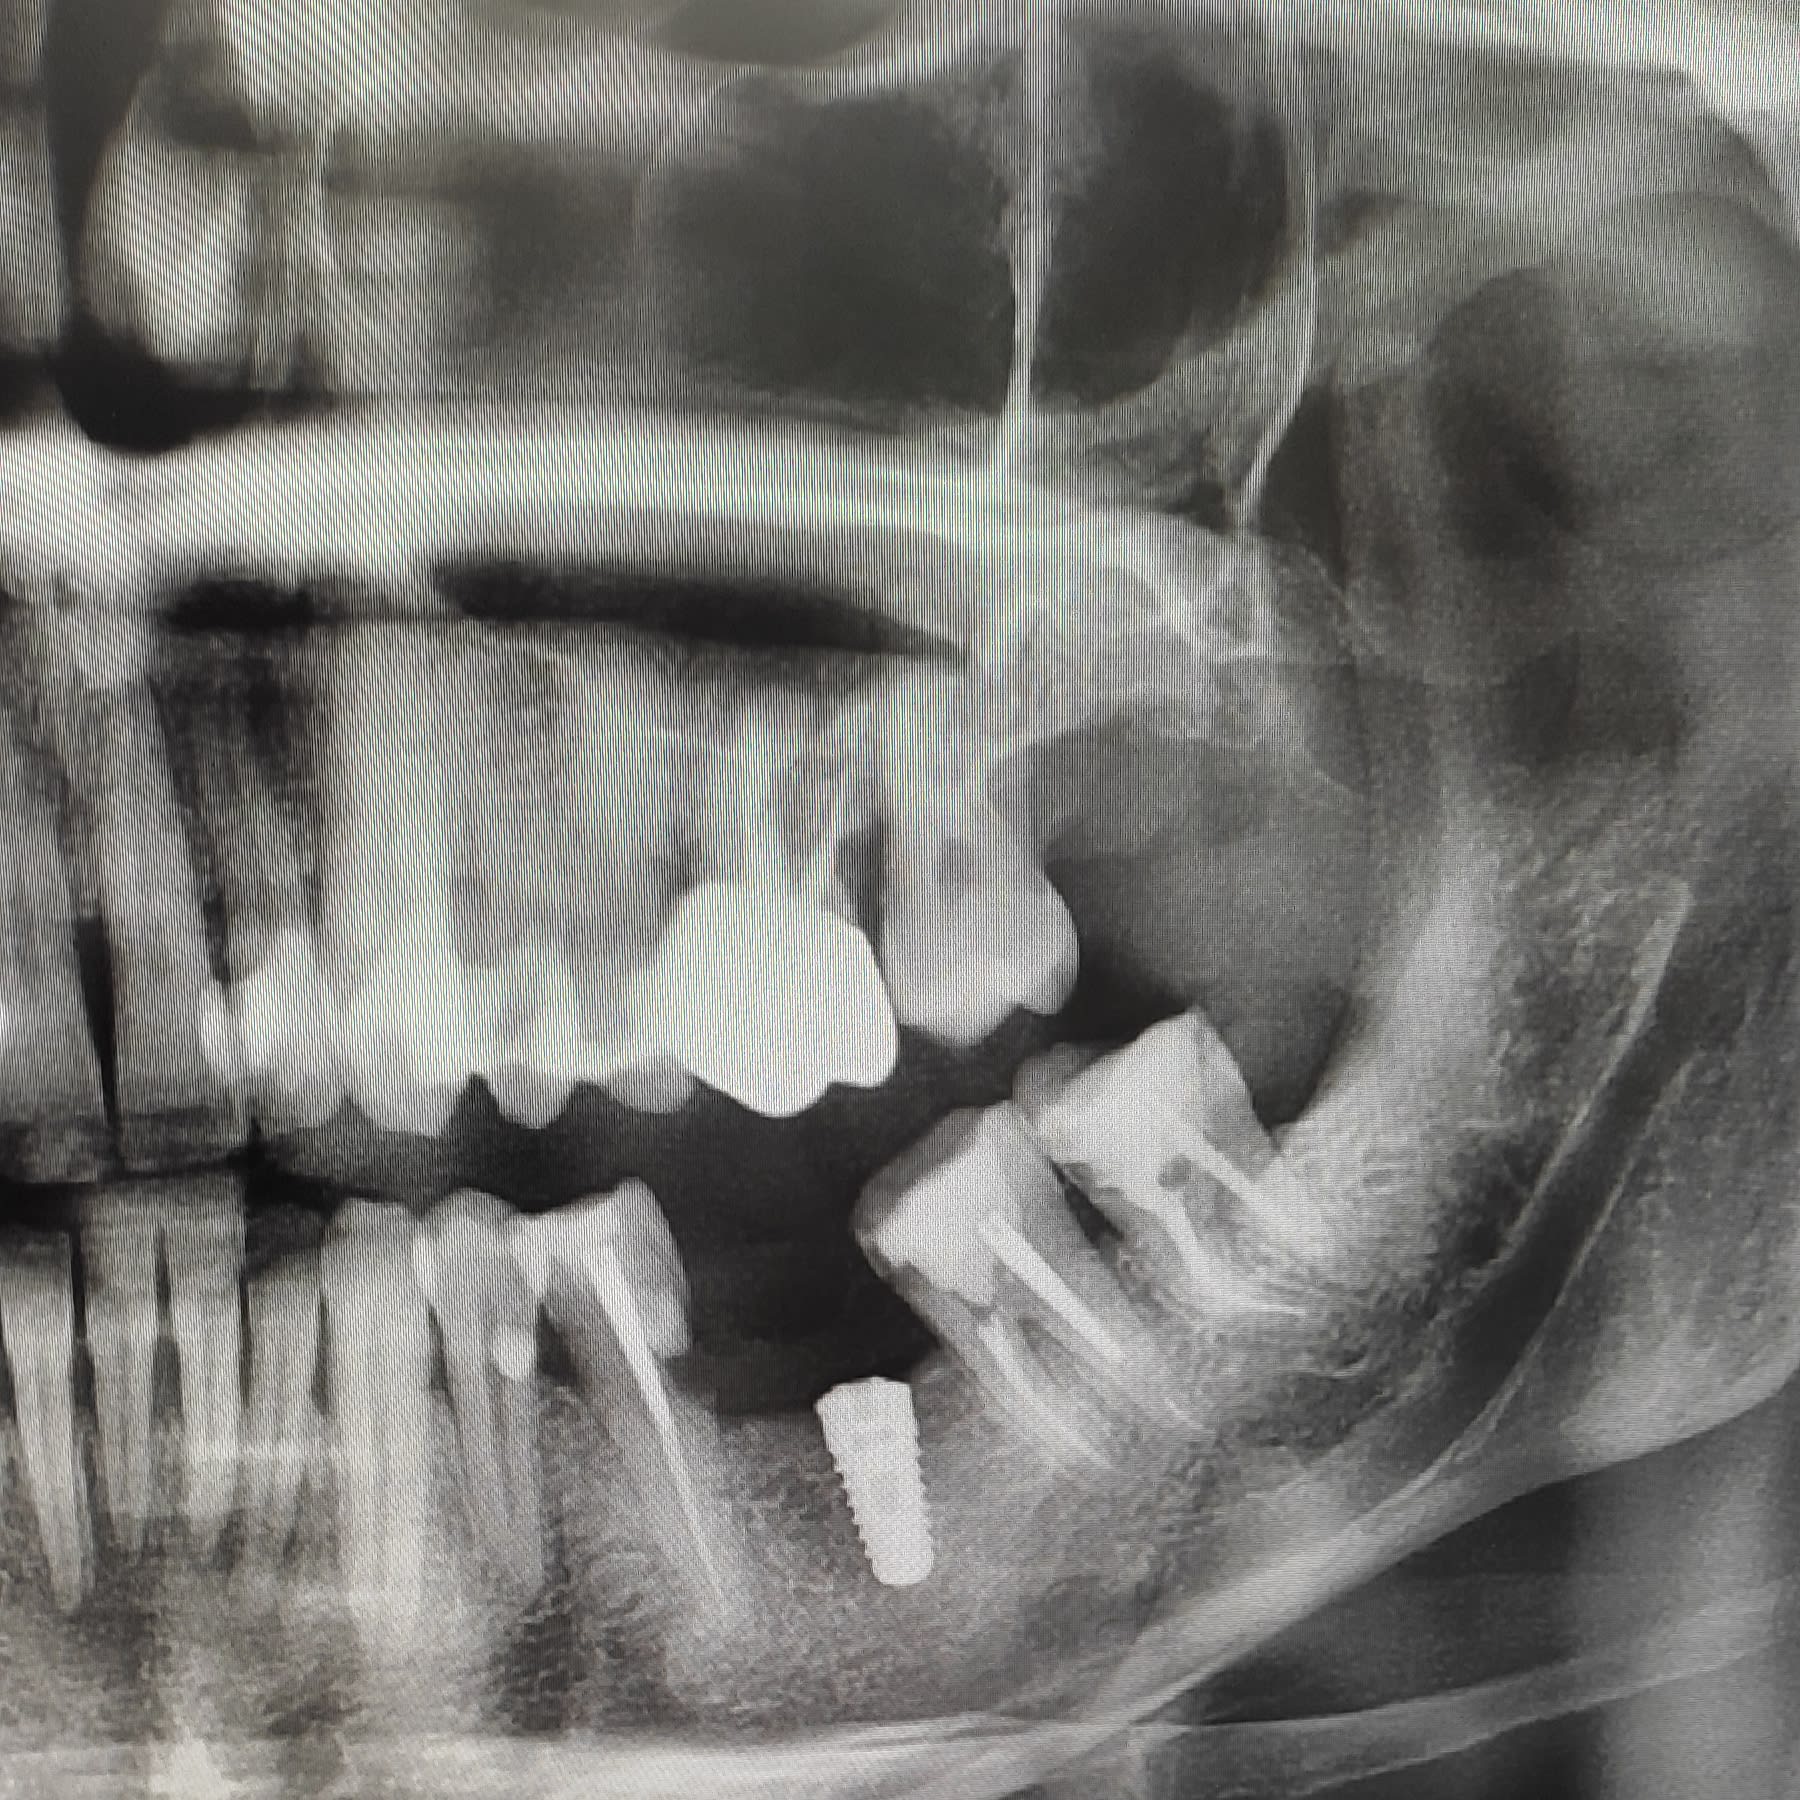

Je veux faire une couronne transvissée sur cet implant ETK.

Quel type de pilier me conseillez-vous pour rattraper l'axe ? Pilier angulé ou pilier Tetra ?

Voilà la pano

D'après la pano, ça ne fonctionnera pas en transvissé.

Tu devrais faire un pilier anatomique sur mesure et une couronne scellée par dessus.

Mais cet implant devrait être un peu plus enfoui.

Ton axe d'implant est en conflit avec la partie mésiale de la 37. Il va falloir rattraper l'axe d'insertion de la couronne avec le pilier. Sauf si tu a prévu de couronner 35 et 37 pour modifier les axes d'insertion.

Il est vrai que j'aurais dû mesialer l'implant, mais en forant, je me suis faite avoir et je suis resté trop perpendiculaire à la mandibule. Et puis la 35 me gênait. La prochaine fois je ferai plus attention.